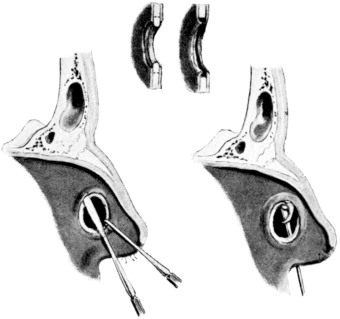

| 210. | Passing the Eustachian Catheter | 365 |

| 211. | Passing the Eustachian Catheter | 365 |

| 212. | Passing the Eustachian Catheter | 366 |

| 213. | Passing the Eustachian Catheter | 366 |